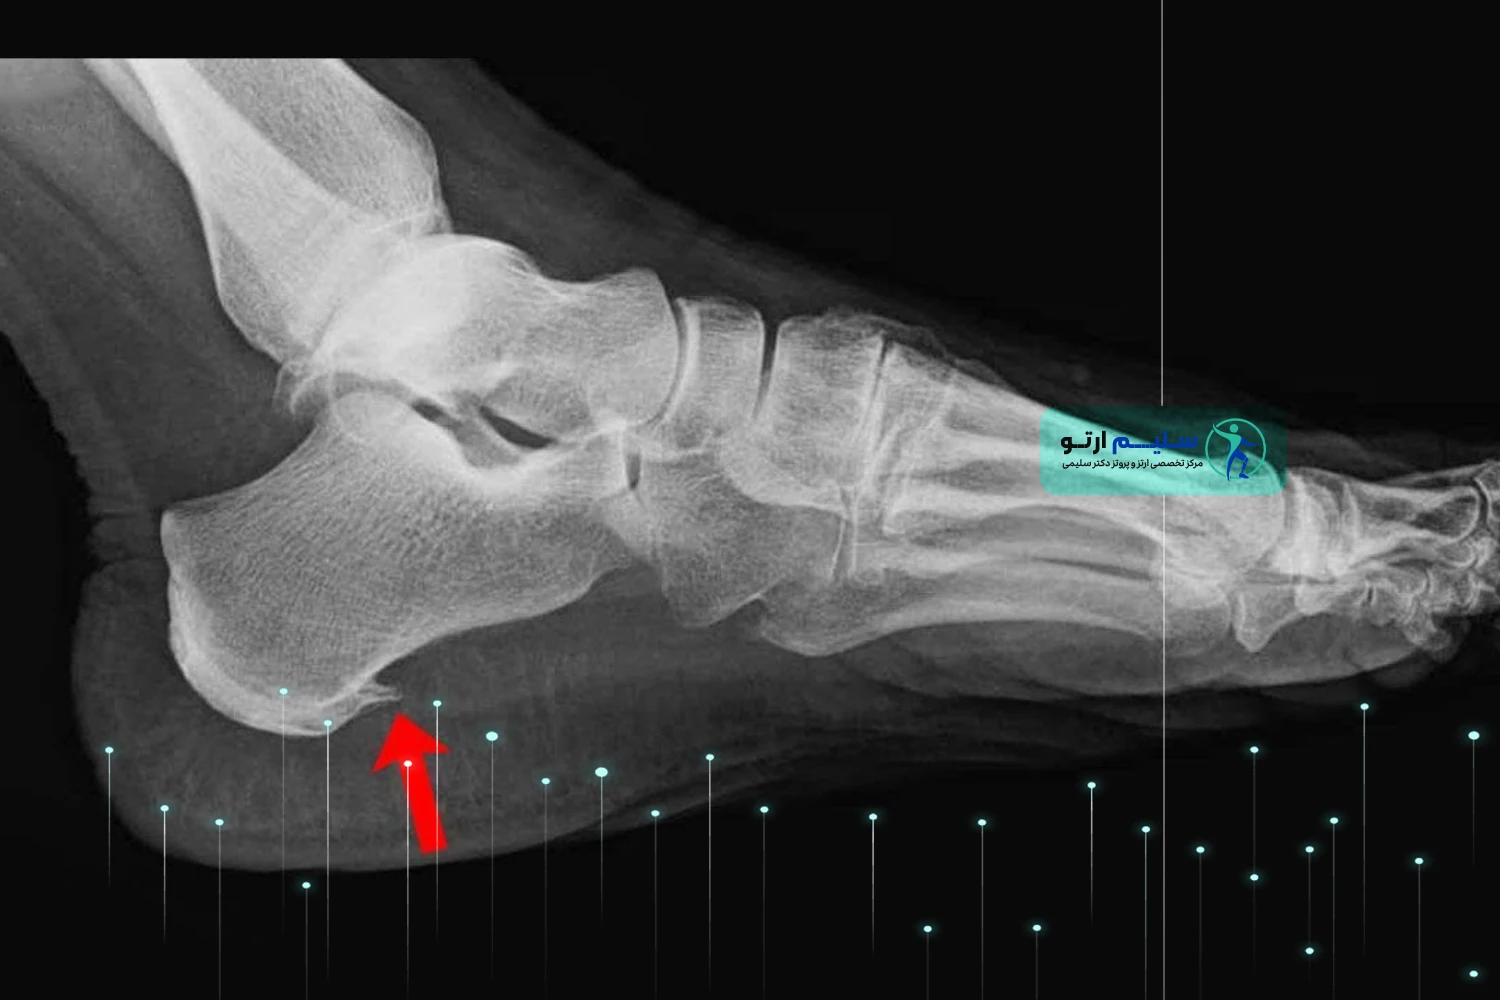

خار پاشنه،که در زبان انگلیسی با نام های “Heel Spur” یا “Calcaneal Spur” شناخته می شود، در واقع رسوبی از کلسیم است که در زیر استخوان پاشنه پا (کالکانئوس) تشکیل می شود. این زائده استخوانی کوچک، می تواند به سمت جلو، به سمت قوس پا،یا در موارد نادرتر، به سمت عقب پاشنه رشد کند.

به بیان ساده، خار پاشنه یک برآمدگی استخوانی کوچک و نوک تیز یا قلاب مانند است که در اثر تجمع تدریجی کلسیم در محل اتصال رباط های کف پا به استخوان پاشنه ایجاد می شود . این زائده نتیجه ی پاسخ طبیعی بدن به فشار و کشش مکرر و طولانی مدت بر روی این ناحیه است . بدن در تلاش برای ترمیم و تقویت بافت های آسیب دیده، شروع به رسوب کلسیم می کند که به مرور زمان منجر به تشکیل این ساختار استخوانی می شود . این عارضه غالباً با پلانتار فاشیئیت (التهاب فاشیای کف پا) همراه است، به طوری که حدود نیمی از بیماران مبتلا به پلانتار فاشیئیت، خار پاشنه نیز دارند.

خیر، وجود خار پاشنه در عکس رادیوگرافی لزوماً به معنای وجود درد نیست . بسیاری از افراد خار پاشنه دارند اما هیچ دردی احساس نمی کنند. درد زمانی ایجاد می شود که این زائده با بافت های نرم اطراف، به خصوص فاشیای پلانتار، برخورد کرده و باعث التهاب و آسیب شود.